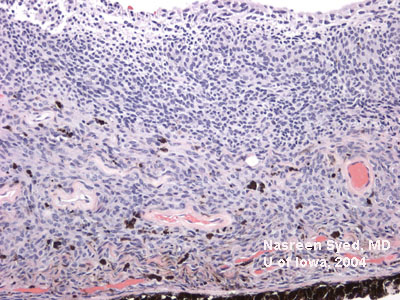

图6:虹膜黑色素瘤的病理图片

低倍镜下被切除的含黑色素瘤的虹膜组织

100倍镜下包含黑色素瘤及痣细胞的瘤组织。细胞为侵袭性的、着色的,并形成巢状。

200倍镜下的瘤组织,漂白去处黑色素。可以看到大的空泡状的细胞核。细胞结构呈异型性。

切片显示瘤组织没有侵入巩膜